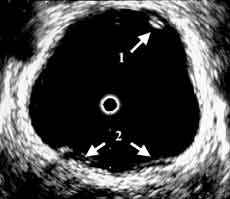

Рис. 2 и 3. Цистэндосонограммы. (Слева) Рак мочевого пузыря стадия Та. 1 - опухоль, 2 - устья мочеточников.

(Справа) Рак мочевого пузыря стадия Т1.